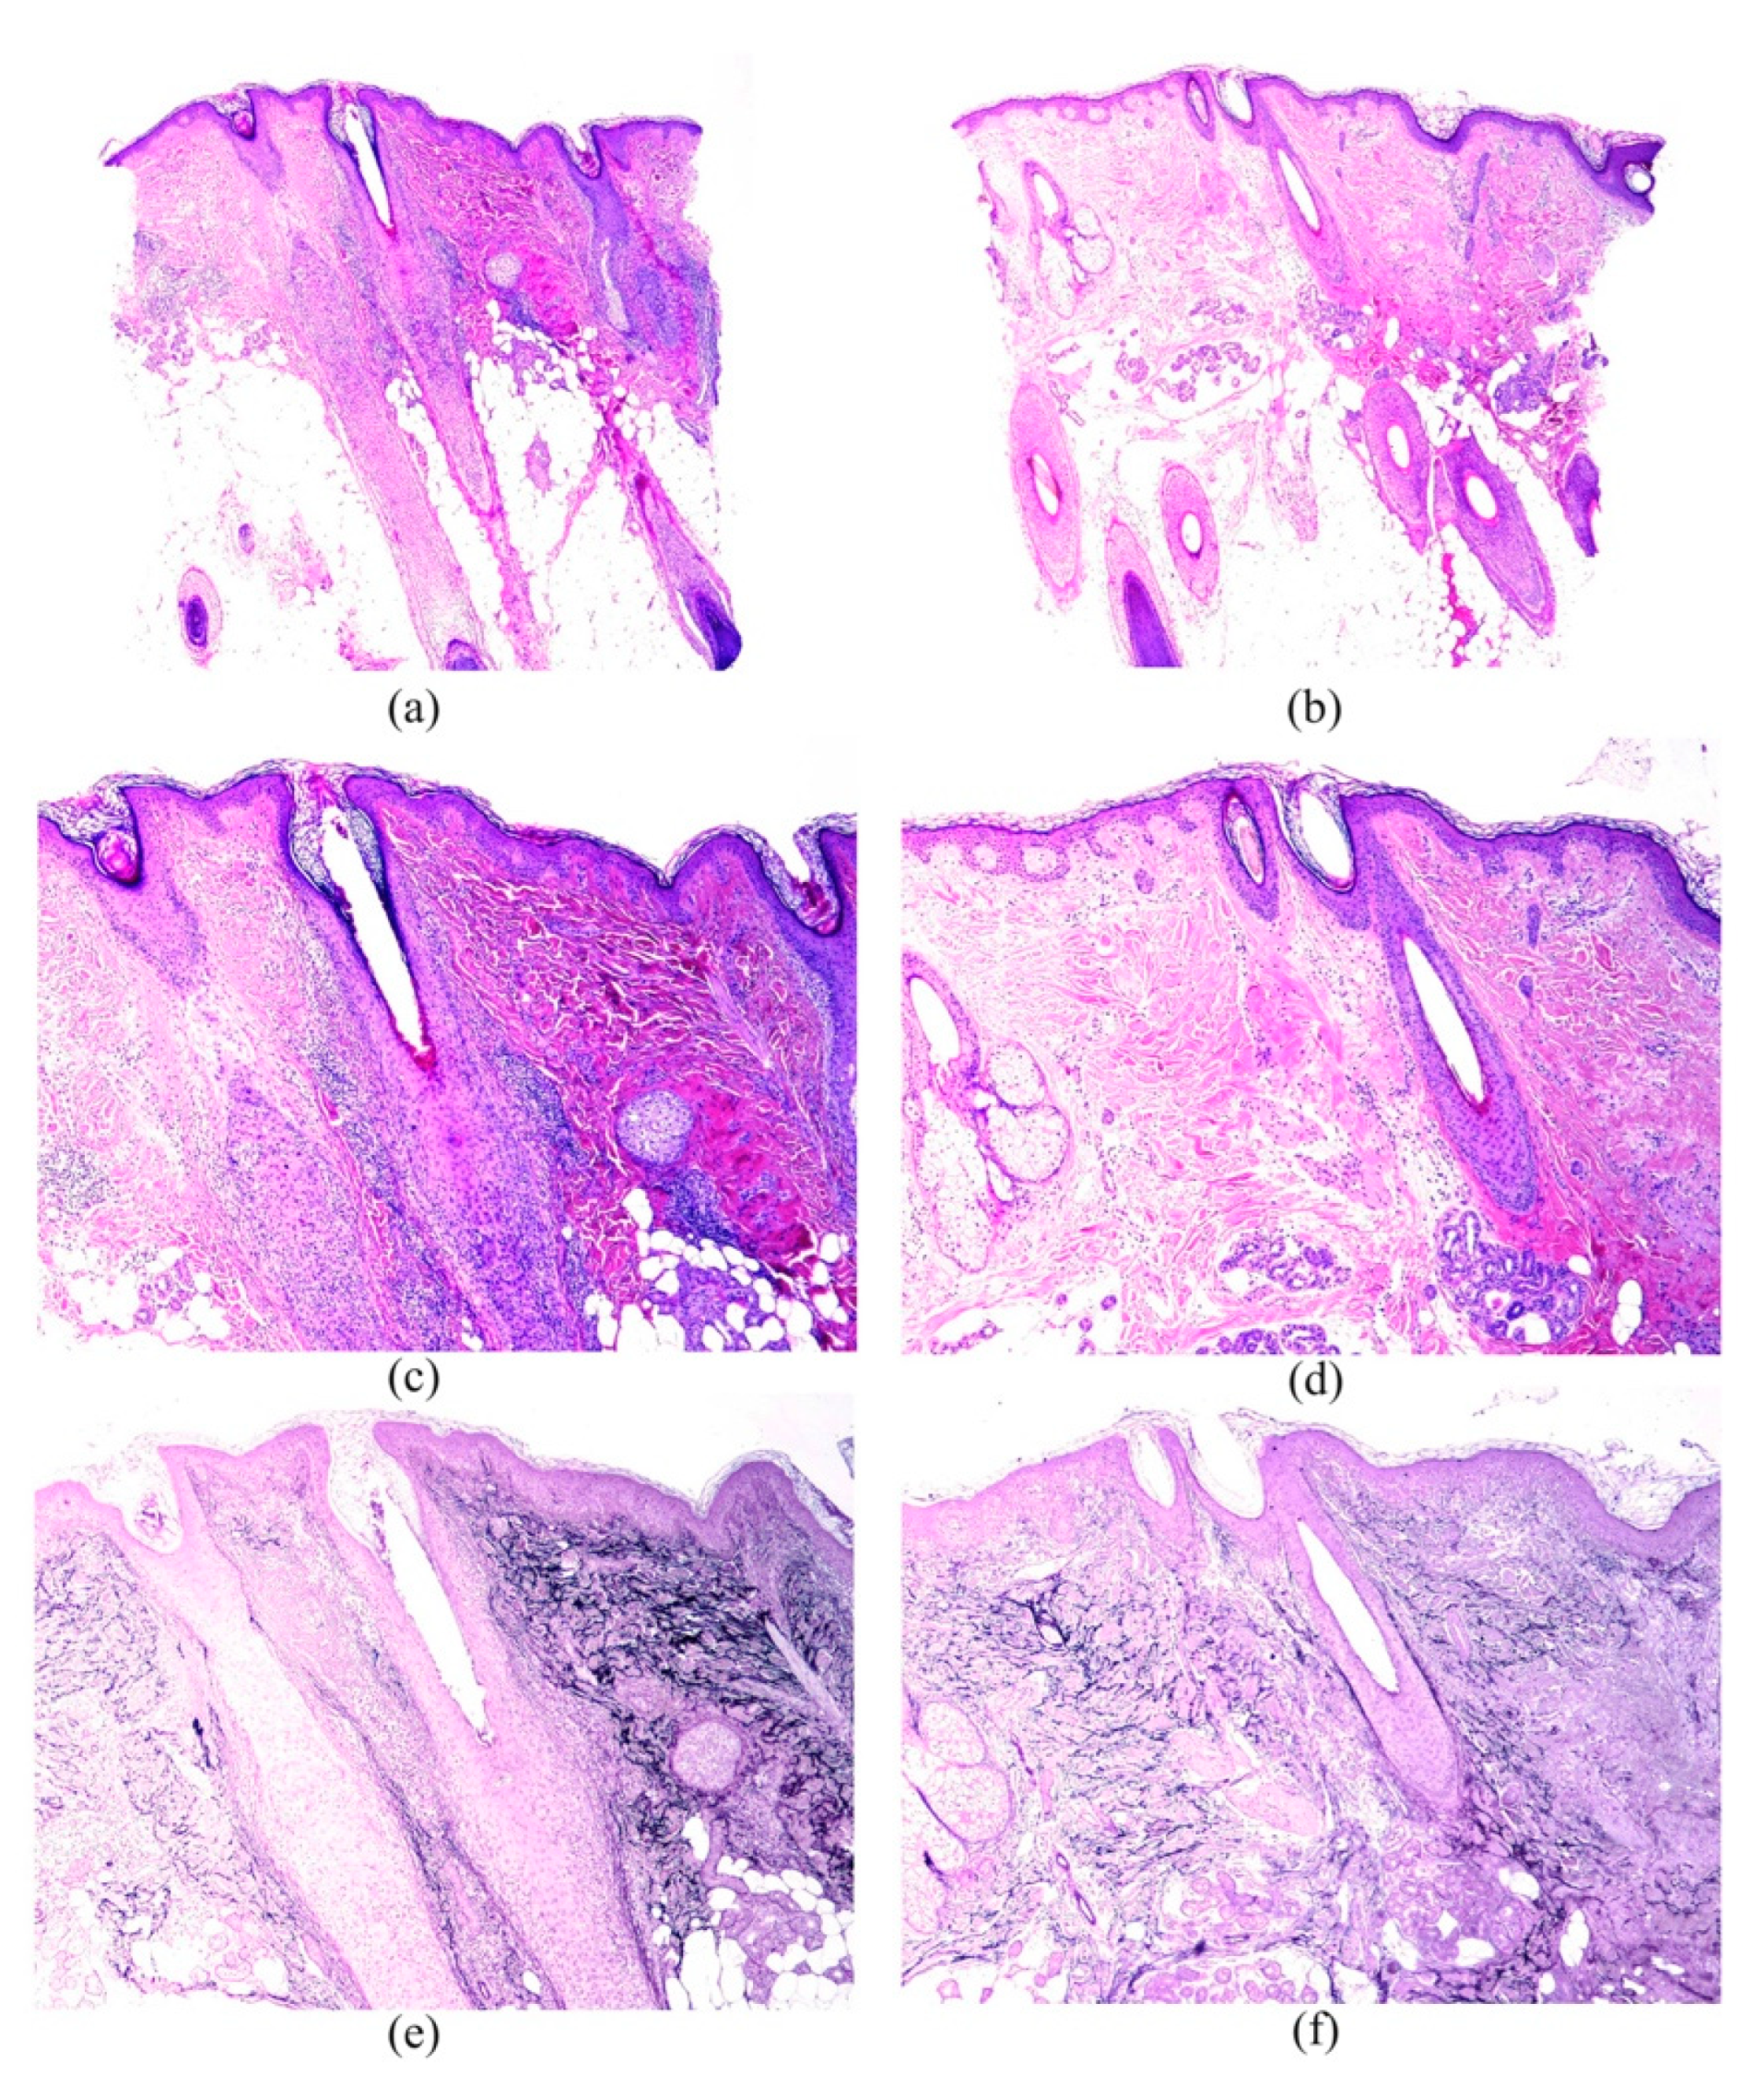

Frontal Fibrosing Alopecia: A Histopathological Comparison of the Frontal Hairline with Normal-Appearing Scalp

3. Results